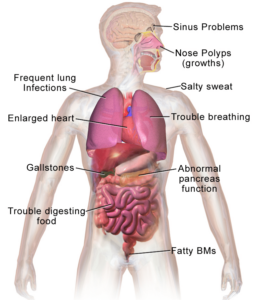

Cystic Fibrosis (CF)

Cheatsheets

2

Mnemonics

0

Images

2

Picmonic

0